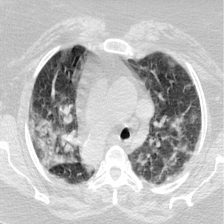

In addition to BM and Gland segmentation, our approach extends to Covid-19 infection segmentation. This task encompasses both binary segmentation, discerning infection presence or absence Fan et al. (2020); Wang et al. (2020); Paluru et al. (2021); Liu et al. (2021a), and multi-class segmentation, which provides a nuanced view by categorizing non-infection, Ground-Glass Opacities (GGO), or Consolidation Zhao et al. (2021); Wang et al. (2022c). Binary segmentation quantifies infection spread in the lungs, while multi-class segmentation offers insights into the infection’s stage, progress, and severity Zhao et al. (2021); Wang et al. (2022c); Bougourzi et al. (2022a). However, the scarcity of data for multi-class Covid-19 segmentation has limited research in this area Zhao et al. (2021); Wang et al. (2022c). The main challenge in segmenting Covid-19 infections arises from their high variability in intensity, shape, position, and type, further complicated by factors such as infection stage, symptoms, and severity Kumar Singh et al. (2021); Laradji et al. (2021). These challenges necessitate an efficient deep learning approach for effectively segmenting Covid-19 infection to save the patients live.

For the Covid-19 infection segmentation task, we evaluated both binary and multi-class segmentation tasks, as summarized in Table 1. Dataset_1 RADIOLOGISTS (2019) consists of 100 slices showing Covid-19 infection, including lungs and multi-class infection masks (GGO and Consolidation). Dataset_2 RADIOLOGISTS (2019) comprises nine 3D CT scans, totaling 829 slices, with 373 slices indicating Covid-19 infection. Expert radiologists labeled this dataset, providing masks for lungs, binary infection (non-infected and infected), and multi-class labels (non-infected, GGO, and Consolidation).

For the binary segmentation task, we divided Dataset_2 into 70%-30% splits for training and testing, respectively. For the multi-class segmentation task, we used Dataset_2 and 50% of Dataset_1 (50 slices) for training, while the remaining 50 slices of Dataset_1 were used for testing. Table 2 summarizes the number of slices for the GGO and Consolidation classes in both the training and testing splits. As shown in the table, the limited number of slices for each class presents a significant challenge for multi-class segmentation.

Figure 7 consists of the visualization of three examples masks using our approach and the comparison architectures for multi-classes Covid-19 segmentation. The first example shows a mixture case of GGO and Consolidation, where most of the infected regions consist of consolidation and small GGO regions are attached to the consolidation regions. Unlike the masks of the comparison architectures, the mask of our approach has a high similarity to the ground truth mask for both the consolidation and GGO classes. The second and third examples also represent a case where both GGO and consolidation are present in both lungs. The infected regions with consolidation are mainly in the lower lobes of both lungs and GGO spreads in both lungs with peripheral and posterior distribution. The masks of these examples confirm the observation in the first example, as the predicted masks of D-TrAttUnet show a high similarity to the GT masks for both infection types GGO and Consolidation.

Slice AttUnet SCOATNet MISSFormer UCTransNet D-TrAttUnet GT

Figure 7: Visual comparison of a segmentation model trained with different segmentation architectures for Multi-classes (No-infection, GGO and Consolidation) Covid-19 infection segmentation using Dataset_2. GGO is presented by the Green color and Consolidation by the red color.